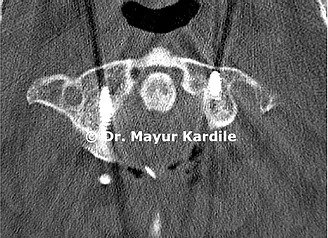

A 61-year-old gentleman with rheumatoid arthritis complaining of neck pain and gait instability. He also had clumsiness of hand movement and spasticity.

Investigations revealed instability between the first and second cervical vertebra causing dynamic compression of the cervical spinal cord.

C1 - C2 stabilization and fusion were done using C1 lateral mass and C2 translaminar screw fixation. Postoperative CT scan and X-ray show good C1 - C2 reduction.